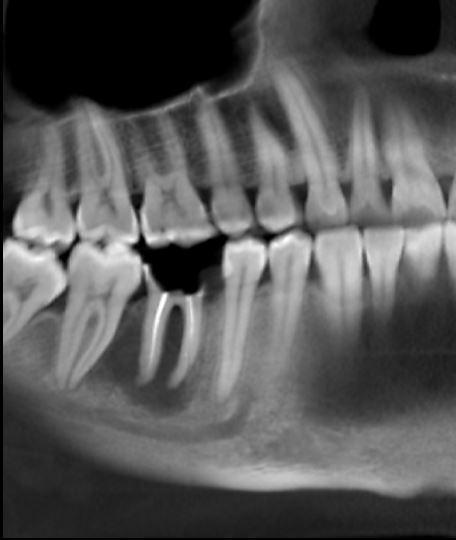

Доброго времени суток. Нужно профессиональное мнение. Два врача говорят только под удаление зуб. Третий - говорит можно попробовать ставить коронку. нужно еще мнение. Как вы считаете? Есть воспаление под зубом. Оно пройдет со временем и стоит подождать и поставить коронку или же тут гиблое дело и под удаление - имплант?